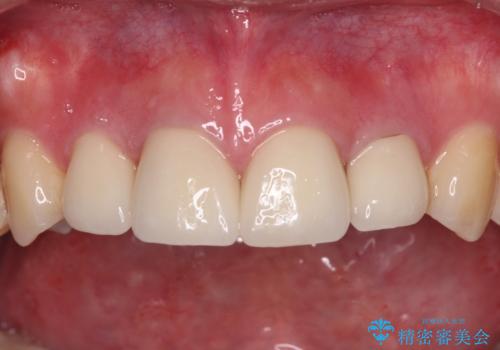

上顎前歯や下顎大臼歯に根管治療の必要な歯がいくつかあるため、矯正治療と並行して根管治療を行い、その後オールセラミッククラウンにて補綴治療を行うこととしました。

開咬の改善には舌突出癖を改善するためのトレーニングが必要ですが、しっかりと行っていただき、想定よりも早い期間で治療を終えることができました。